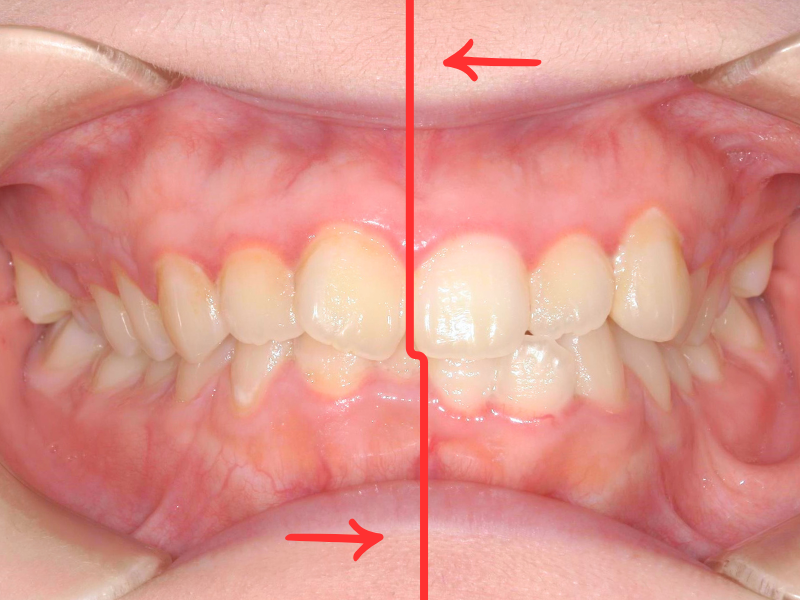

20代、女性、マウスピース

| 施術内容 | 主訴:噛み合わせが深い、真ん中の線が合っていない 詳細:マウスピース矯正を装着しての歯並び改善 |

|---|---|

| 治療期間 | 10ヶ月(9/26現在 治療終了) |

| リスク・副作用 | ■リスク・副作用 ・治療の初期段階では、痛みや不快感が生じやすくなりますが、一週間前後で慣れます。 ・歯の動き方には個人差があるため、予想された治療期間より延長する場合があります。 |

| 費用 | 枚数無制限 48万(税込528,000円) |